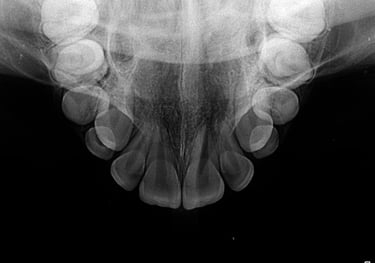

RADIOGRAFIA OCLUSAL